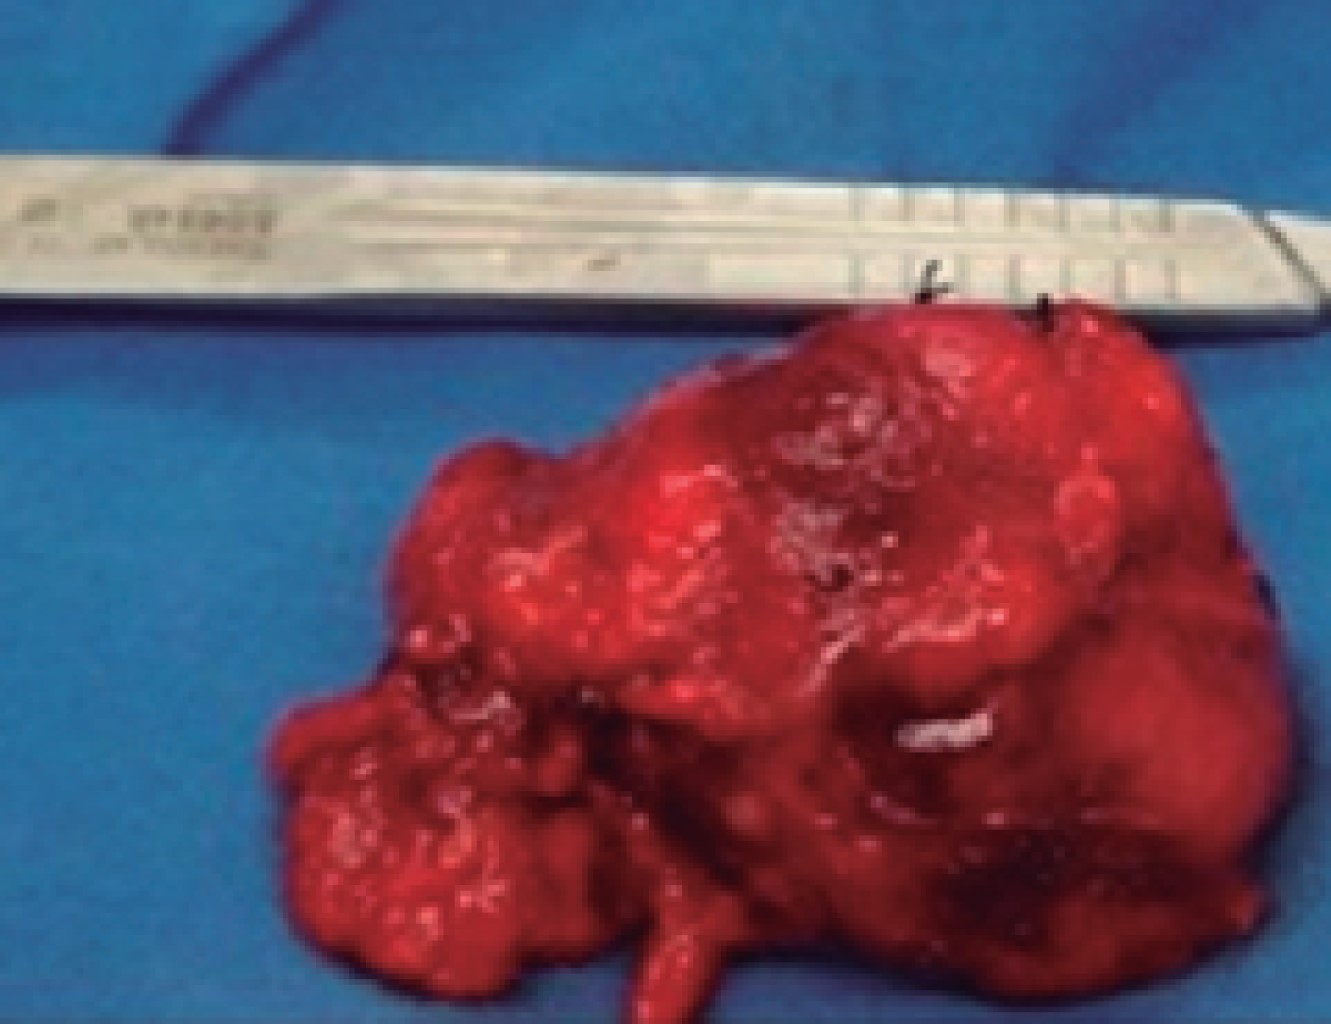

A right posterolateral thoracotomy was performed because we did not have equipment to perform minimally invasive surgery, finding a tumor in the middle mediastinum of approximately 7 × 5 × 4 cm, with a hard consistency, encapsulated, and attached to the lateral wall to the superior vena cava, upper edge of the azygos vein and intrathoracic trachea, and to its lower portion to the azygos vein (Figure 2). The tumor was completely excised (Figure 3). In the immediate postoperative period, the patient showed no complications and was extubated. The control thoracic X-ray showed complete pulmonary expansion (Figure 4).

Macroscopically, histopathology evaluation showed an encapsulated tumor with scarce adherent fibroadipose tissue and fine vascular tracts. The histopathological diagnosis was Castleman's disease, of the hyaline vascular type, with reactive hyperplasia of dendritic cells. The antibody panel performed for CK AE1/AE3 was negative and positive for CD21.

Figure 3